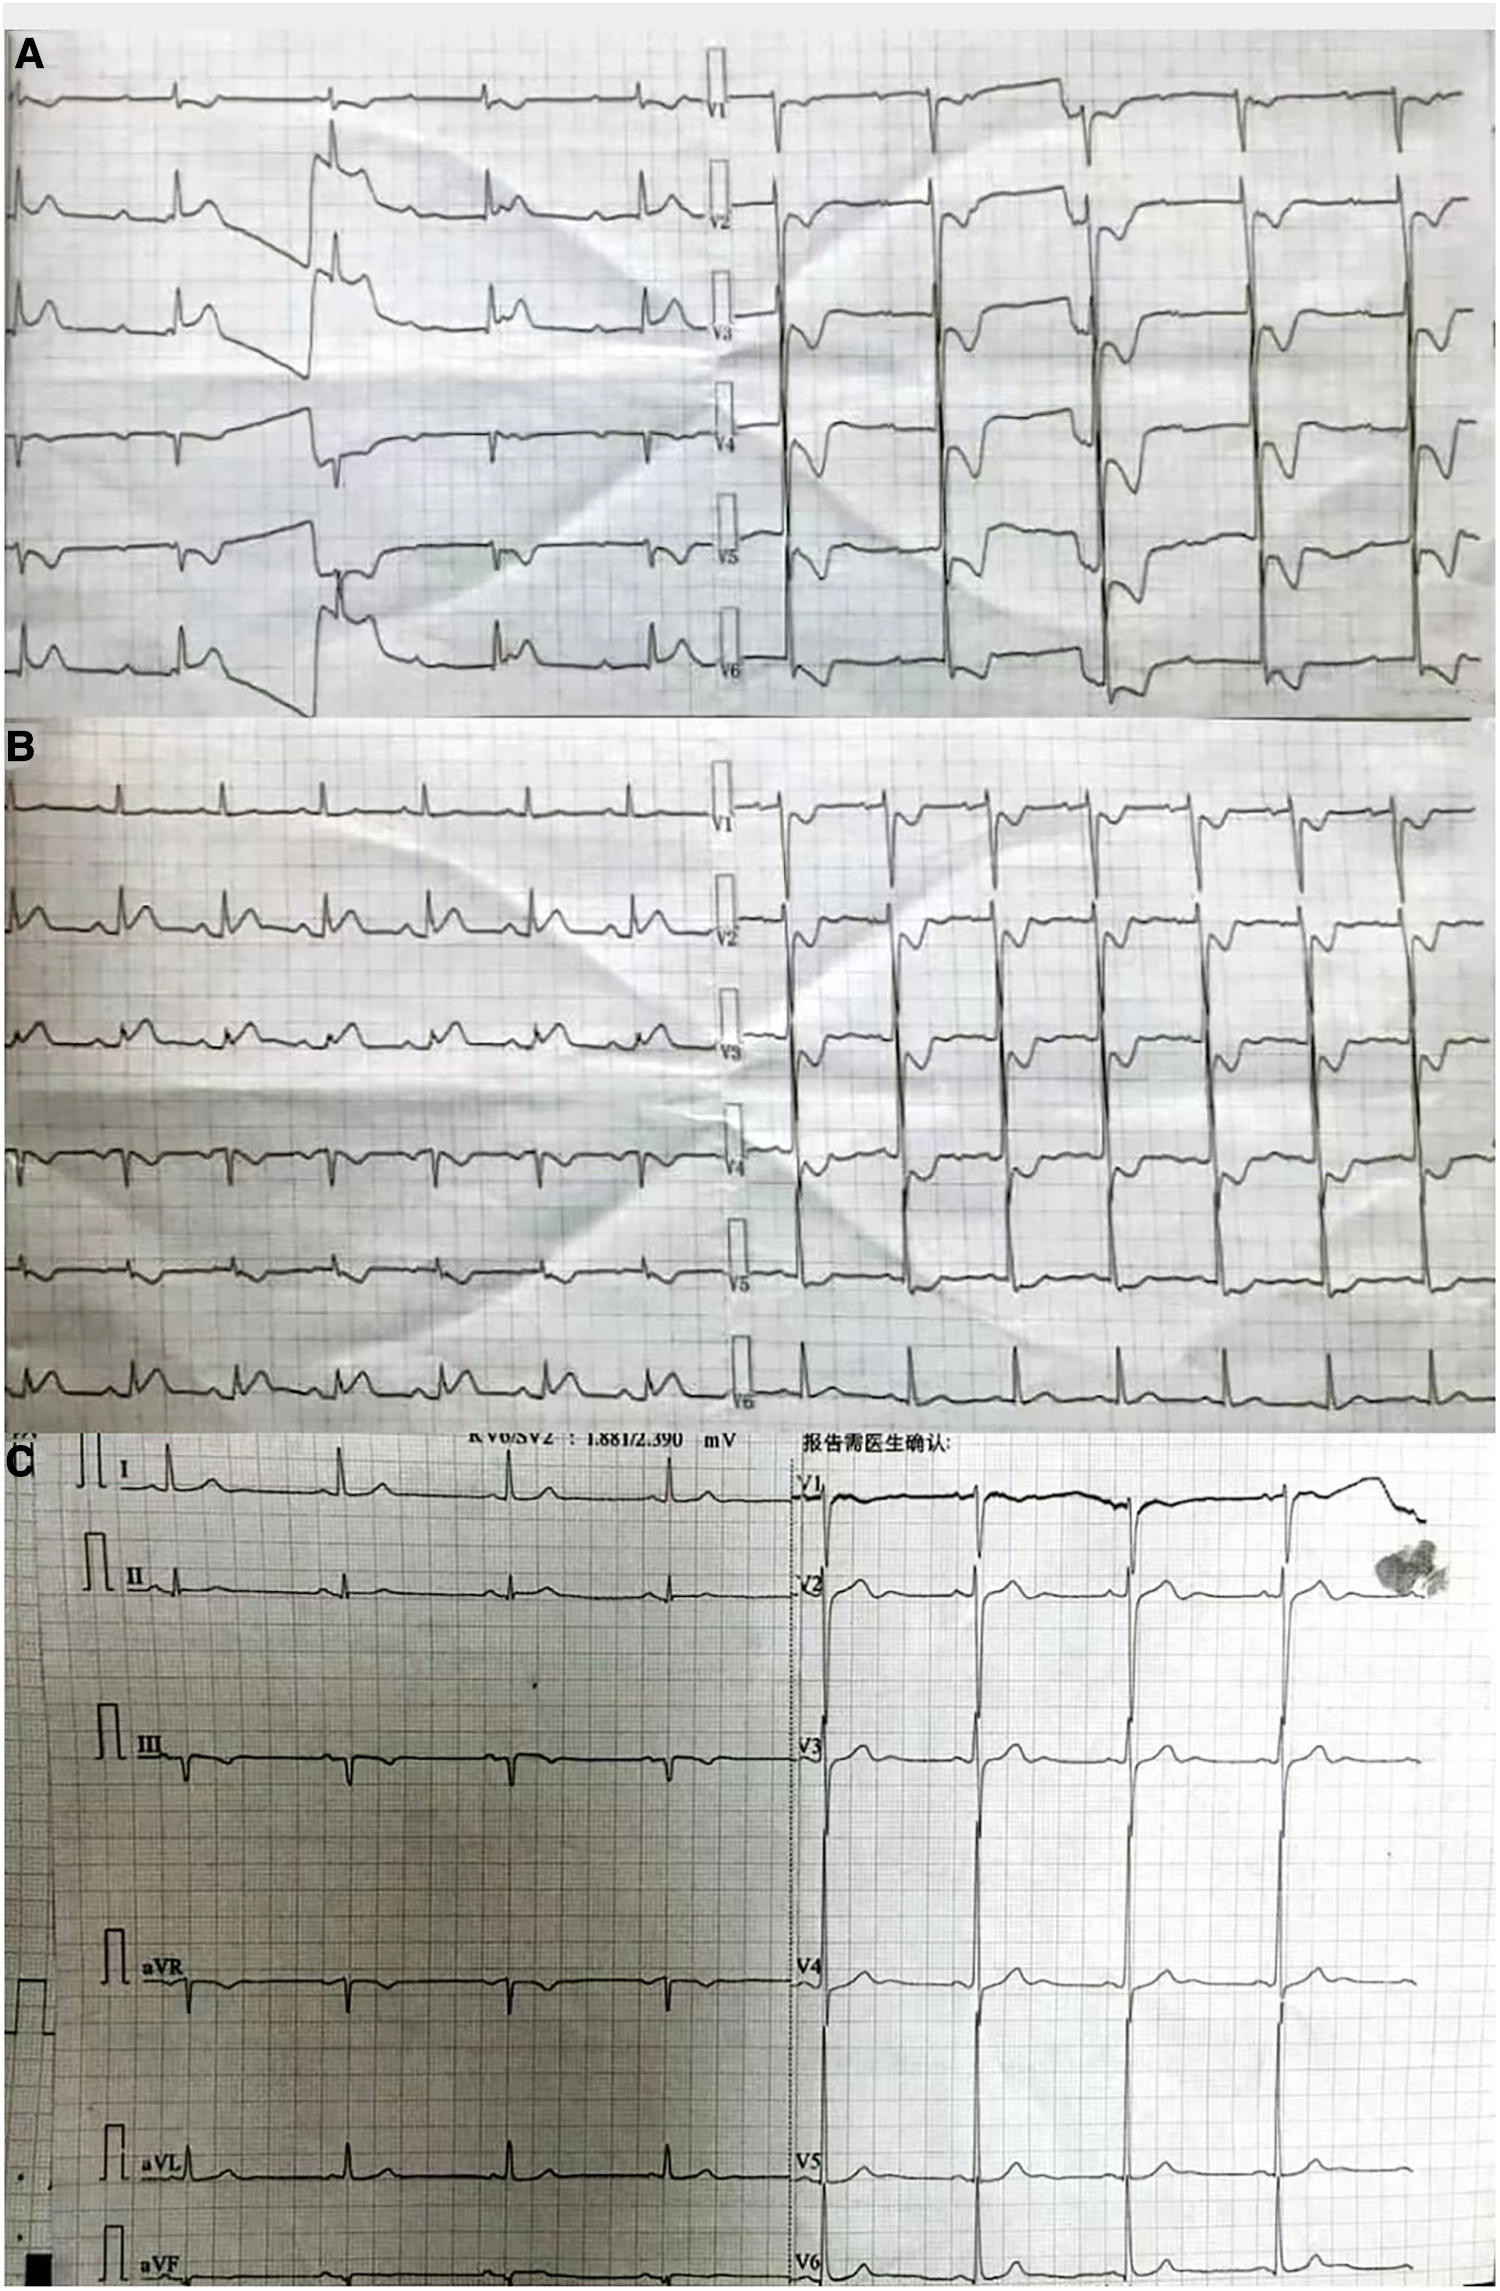

A 54-year-old man was transferred from the local hospital to our hospital's chest pain center in the emergency department due to suspected AMI. The ECG obtained at the local hospital showed ST-segment elevation in the inferior wall leads (II, III, and aVF), indicating possible damage to the heart muscle in that area and a complete atrioventricular block (Figure 1A). When the patient arrived at our emergency department, another ECG was performed, which showed a sinus rhythm with ST-segment elevation in the inferior wall leads (Figure 1B). The patient did not exhibit obvious difficulty in breathing. The laboratory results showed a high percentage of neutrophils (84.3%), indicating an inflammatory response in the body. Furthermore, the results of biomarker analysis were as follows: cardiac troponin-T (cTnT) level, 474.4 ng/L; myoglobin (Mb) level, 565.30 ng/ml; creatine kinase MB (CK-MB) level, 108.00 ng/ml; and brain natriuretic peptide level, 264 pg/ml. Moreover, the patient underwent general cranial computed tomography (CT) scans (Figures 2A–C) and chest CT scans (Figures 2D–F) to assess any further complications or conditions.

Figure 1

(A) ECG obtained at the local hospital. The findings suggest that the patient has been diagnosed with third-degree atrioventricular block. In addition, there are significant ST segment elevations observed in leads II, III, and aVF, and inverted T waves seen in leads V1–V6, accompanied by ST-segment depression. (B) ECG obtained at the emergency department of our hospital. The findings suggest that the patient has a sinus rhythm. There are inverted T waves observed in leads V1–V4, accompanied by a lesser degree of ST-segment depression. (C) ECG obtained at the Department of Cardiology of our hospital. The findings indicate left ventricular high voltage. There is a resolution observed in the ST segments of leads II, III, and aVF.

ECG plays a crucial role in both differentiating PE from other conditions and distinguishing it from AMI to some extent. In the case of PE, the presence of T-wave inversions and ST-segment depressions in leads V1–V3 is indicative, whereas these ECG changes in leads V4–V6 suggest AMI. However, in the current case, T-wave inversions and ST-segment depressions were observed in leads V1–V6, making the diagnosis more challenging. The occurrence of PE with Ⅲ° AVB is rare, with only a few reported cases found in the available literature (1, 6, 7). The occurrence of Ⅲ° AVB may be attributed to a preexisting left bundle branch block (LBBB). Notably, Ⅲ° AVB is the combination of a preexisting LBBB and an emerging RBBB. In the present case, the patient had a history of hypertension, which can cause ICH and LV hypertrophy, making him more likely to develop LBBB. However, it was difficult to determine whether the patient had RBBB or LBBB. Another possible explanation for the occurrence of Ⅲ° AVB could be ischemic injury to the atrioventricular node (AVN). The AVN receives its blood supply primarily from the AVN branch of the right coronary artery in approximately 90% of individuals (8). Therefore, the low perfusion of the coronary artery and potential coronary spasm could have led to dysfunction in the AVN, further contributing to the development of Ⅲ° AVB.

Large PE, particularly in the form of pulmonary artery trunk embolism or involving the left and right proximal pulmonary arteries, can at times present solely as III° AVB. In such cases, sudden death is often the main manifestation, making it challenging to save these patients if they do not reach the hospital in time. Consequently, encounters with cases of PE combined with III° AVB are relatively rare in clinical settings. In the case of the patient in question, the ECG obtained upon arrival at the emergency department demonstrated a sinus heart rate and ST elevation in the inferior wall. Additionally, the III° AVB had resolved, and the patient's dyspnea had improved. We speculated that the large embolus blocking the pulmonary artery may have turned into multiple small emboli because of bumpy transportation and that spontaneous fibrinolysis may be a possible etiology. This could explain the improvement of dyspnea and disappearance of Ⅲ° AVB.